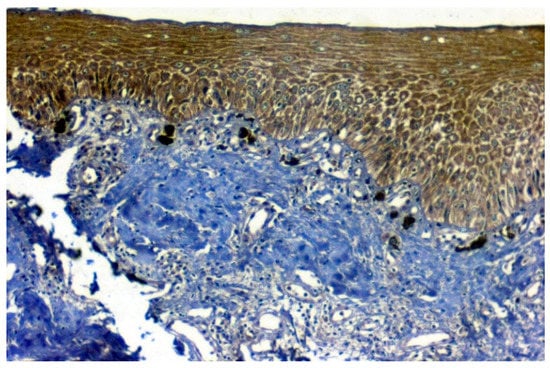

Positive immunoexpression for CA 1 was found in 70.4% (88/125). Among the 40 patients with OSCC, CA 1 overexpression was found in 75% (30/40), and among the OSMF patients, CA 1 overexpression was found in 77.8% (56/72) compared to 15.4% (2/13) of normal, which was found to be statistically significant (p = 0.000; χ2 = 21.169) (Table 3). Based on different degrees of epithelial abnormalities, we found a statistically significant association (p = 0.025; χ2 = 11.144). Our results showed epithelial atrophy among the OSMF patients showing positive CA 1 overexpression. There was no significant association between CA 1 expression and degrees of inflammation, fibrosis and vascularity. Figure 4 shows the negative immunoexpression of CA1 in normal samples. Figure 5 shows the CA 1-positive immunoexpression in epithelial cells in OSMF samples, with cytoplasmic and nuclear positivity. In OSCC samples, CA 1 demonstrates strong cytoplasmic and nuclear positivity in malignant epithelial cells (Figure 6).

Figure 4.

IHC for CA 1 in normal samples (under 20× magnification).

Figure 5.

IHC of CA 1 in OSMF samples (under 20× magnification).